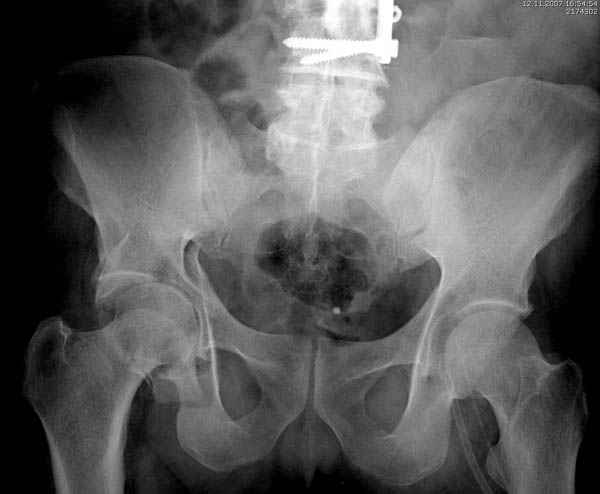

Дополнительно имеется перелом ацетабулума: задняя

колонна с полупоперечным переломом, и переломы костей лица.

На седьмой день зафиксирован перелом ацетабулума через задний доступ. Перед операцией для профилактики DVT, IVC фильтер, также получает Lovenox.

Там множество обычных 2.7 мм шурупов, потом идет фиксация основными пластинами.

Снимки здесь....